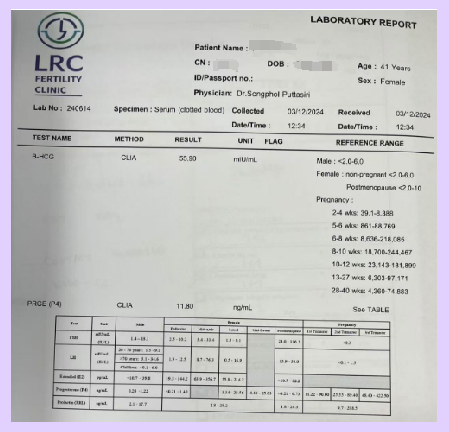

| Gestational Age | B-hCG (mIU/mL) | Progesterone (ng/mL) | Ultrasound Findings |

|---|---|---|---|

| 4 weeks + 5 days | 55.9 | 11.8 | – |

| 5 weeks | 41,759 | 15.06 | Gestational sac: 24×18×10 mm, yolk sac: 3.3 mm, no fetal heartbeat or embryo visible |

| 6 weeks | – | – | Gestational sac: 30×22×19 mm, yolk sac: 3.1 mm, fetal heartbeat and embryo (5×3 mm) visible |

▲ Ms. A’s pregnancy test report